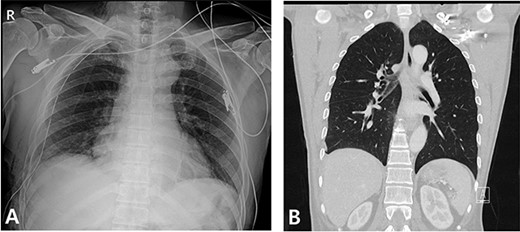

A 59-year-old man was admitted with multiple rib fractures and liver contusion due to a fall injury. He was standing on a chair for working at a farm, and it was knocked over causing him to fall and hit his flank against the corner of the chair. There was continuous pain while resting at the right flank and severe pain with pressure was noted, but no external wounds or bruises were observed. There were right 7th–11th rib fractures, scanty pneumothorax, minimal hemothorax and a 2-cm-sized liver contusion in abdomen and chest computed tomography (CT) scan (Fig. 1A, B). He was hospitalized for pain control and close observation in the general ward, and conservative management was initiated. Also, no significant changes were noted in the following daily follow-up chest radiographs. The patient suddenly complained of right-sided chest and back pain aggravation, cold sweating and fatigue 80 h after the traumatic injury. His mental status was alert, but v/s including systolic blood pressure (SBP) of 100–120 mmHg, heart rate (HR) of 40-60 beats/min and oxygen saturation of 100% during the admission changed to an SBP of 86/60 mmHg, HR of 88 beats/min and oxygen saturation of 97% when the symptoms occurred. Chest radiography was performed after the patient experienced aggravated symptoms, such as right-sided flank pain, cold sweating and fatigue. Compared to the previous scans, signs of increased opacification and peribronchial and parenchymal infiltrations were observed, which were indicative of hemothorax (Fig. 2A, B). We performed enhanced dynamic chest CT to identify any presence of active bleeding. On the chest CT scan, a large amount of hemothorax was identified in the right lung field along with multiple fractures of the right ribs. However, there were no signs of contrast leakage indicative of active bleeding (Fig. 3). Hemoglobin levels decreased from 13.1 g/dl on the day before the symptoms appeared to 11.5 g/dl at the onset of symptoms and to 9.4 g/dl after 2 h. Four packs of RBC transfusion and fluid were administered to the patient, and he was moved to the intensive care unit for close monitoring. And tube thoracostomy was performed, and 1600 ml of fresh blood was drained (Fig. 4A). The following day, 500 ml of blood was drained through the chest tube, but his v/s were stable (Fig. 4B). The amount of bleeding through the chest tube was decreased, but the drained fluid was fresh blood. And we thought that the remaining hematoma was not effectively drained, so the patient’s respiratory discomfort could persist and cause uneffective ventilation. And then we consulted with the Department of Thoracic Surgery, and video-assisted thoracoscopic surgery (VATS) exploratory thoracotomy was performed to identify the bleeding source caused by displaced rib and evacuate the large amount of hematoma. There was a large volume of hematoma within the pleural space and between the right lower lobe, diaphragm and fissure, but no active bleeding point was located. The fractured right 10th rib pierced through the pleural space and was displaced to the thoracic cavity, which was easily reduced. There was no injury surrounding the diaphragm, and although the general lung and chest wall contusions were severe, there were no signs of lung parenchymal lacerations (Fig. 5A–C). Chest tube drainage was serous, and there was no further bleeding. There were no signs of bleeding or any other abnormal findings on chest CT performed at the outpatient clinic, and the patient had no complaints of any symptoms (Fig. 6A, B).

Radiographic findings. (A) Initial chest X-ray showed no evidence of hemothorax. (B) Initial chest CT also showed no evidence of hemothorax.